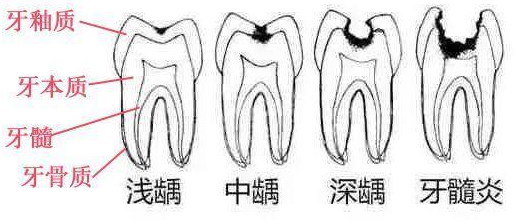

ЁЁЁЁбРвНЫЕЃК“ШЃВЁЪЧгЩвдЯИОњЮЊжїЕФЖрвђЫиЕМжТЕФбРГнгВзщжЏЗЂЩњТ§адНјааадЦЦЛЕЕФвЛжжМВВЁЁЃвбОПЊЪМЧГШЃМДбРгджЪШЃЃЌашвЊзівЉЮяжЮСЦЛђГфЬюжЮСЦЁЃ

ЁЁЁЁбРвНШДЫЕЃК“етЪБВЁБфвбОЦЦЛЕЕНбРБОжЪЧГВуСЫЃЌбРГнвбОгаШЃЖДаЮГЩЃЌЖдЫсЬ№ЪГЮяУєИаЃЌашвЊзіГфЬюжЮСЦЁЃ”

ЁЁЁЁбРвНИцНыЫЕЃК“ВЁБфвбОЦЦЛЕЕНСЫбРБОжЪЩюВуЃЌбРГнгаНЯЩюЕФШЃЖДЃЌЮТЖШДЬМЄЃЌЛЏбЇДЬМЄвдМАЪГЮяНјШыШЃЖДЪБОљв§Ц№ЬлЭДЃЌДЫЪБЃЌМАЪБзіГфЬюжЮСЦЕФЛАЛЙРДЕУМАБЃзЁбРЫшЁЃ”

ЁЁЁЁбРвНШДзХМБЕиЫЕЃК“бРГнМБадИљМтжмбзИаШОПЩФмв§Ц№МфЯЖИаШОЃЌбЯжиЕФЛсЮЃМАЩњУќЁЃДЫЪБЃЌашвЊЕНе§ЙцПкЧЛвНдКжЮСЦЛМбРЃЌХфКЯвЉЮяжЮСЦЃЌБивЊЪБзіХЇжзЧаПЊв§СїЪѕЁЃ”